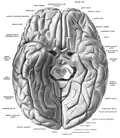

![]() Глазничная поверхность левой лобной доли | |

Прямая извилина (лат. gyrus rectus; англ. straight gyrus, StG) — извилина в нижней части лобной доли, расположенная между медиальной обонятельной бороздой и медиальным краем полушария. Соответствует медиальной части цитоархитектонического поля Бродмана 11.